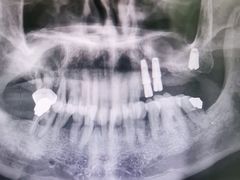

• 牙博士口腔品牌连锁(杨浦店)

• -牙博士口腔品牌连锁(杨浦店)

小明 | 21-11-08